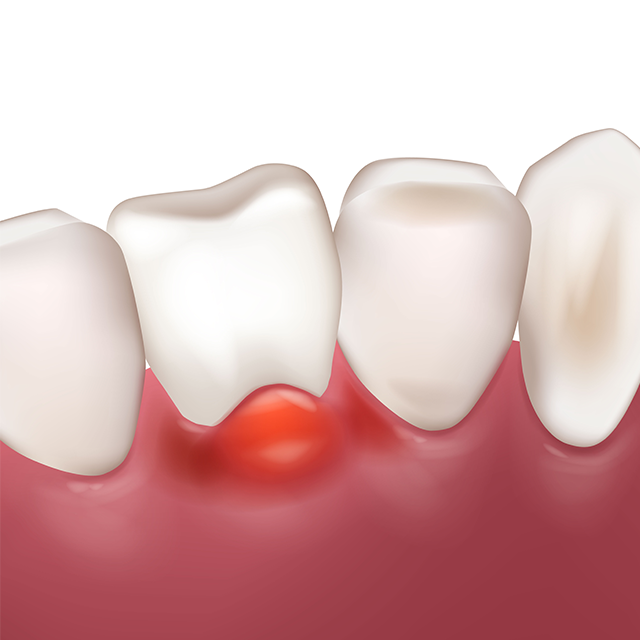

• STEP 03

치수염 충치

• 치아신경(치수)에 염증 발생

• 심한 치통 반복

• 치료 중간 통증이 멈추지만 재발

가능성이 높아 꾸준한 치료 필요

인레이 / 온레이